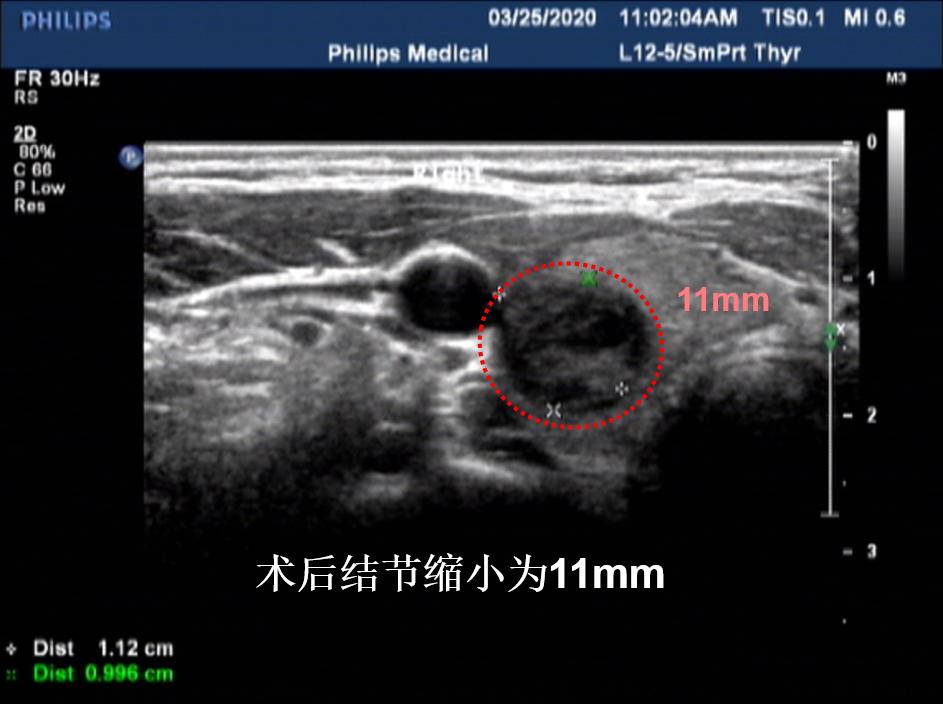

病例④: 3cm的甲状腺结节微创消融术后2月

微创消融前后超声对比,体积缩小99%